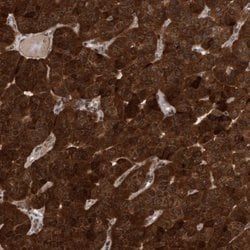

| Immunohistochemistry (Paraffin), Immunocytochemistry | |